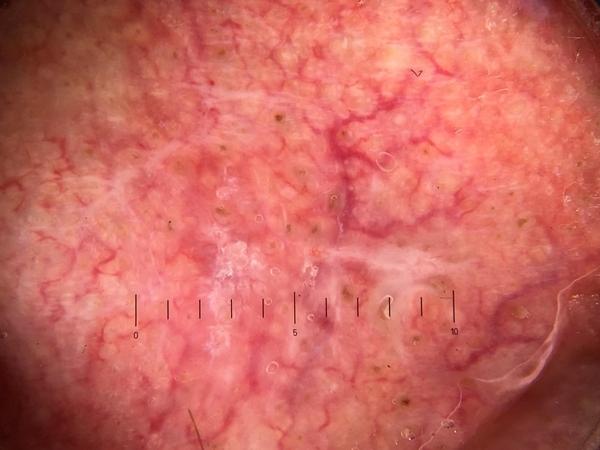

MILK10k consists of 10480 images, each representing a paired clinical close-up and dermatoscopic image for 5240 lesions. The dataset’s metadata include age (in 5-year intervals), sex, anatomic site, skin tone, diagnosis, method of ground truth establishment (histopathology or other means), and, if a dermatoscopic image of the same lesion was previously included in ISIC, its corresponding ISIC identifier. Skin tone is categorized into six levels, ranging from very dark (0) to very light (5), intentionally distinct from the Fitzpatrick skin types to avoid confusion. Most patients had skin tones in the middle ranges. Of the 5240 lesions, 95.7% were biopsied or excised, with histopathology serving as the gold standard for diagnosis. Diagnoses were mapped to both the ISIC-Dx diagnostic scheme and a simplified classification based on the ISIC2018/2019 challenge and HAM10000 diagnostic categories. The dataset includes 11 broad diagnostic categories:

Additionally, we provide the most specific ISIC-Dx diagnosis and its parent branch in the ISIC-Dx diagnostic tree. In cases where a dermatoscopic image of the same lesion was already included in the ISIC archive, its ISIC identifier is reported in the metadata. Furthermore, all images have been annotated using the MONET framework, with probabilities for the following concept term groups included in the metadata: